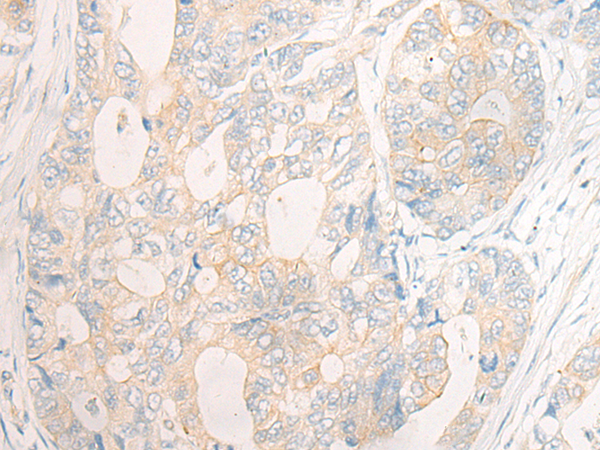

The image is immunohistochemistry of paraffin-embedded Human liver cancer tissue using 47074(DOCK11 Antibody) at dilution 1/35. (Original magnification: ?00)

The image is immunohistochemistry of paraffin-embedded Human gastric cancer tissue using 47074(DOCK11 Antibody) at dilution 1/35. (Original magnification: ?00)